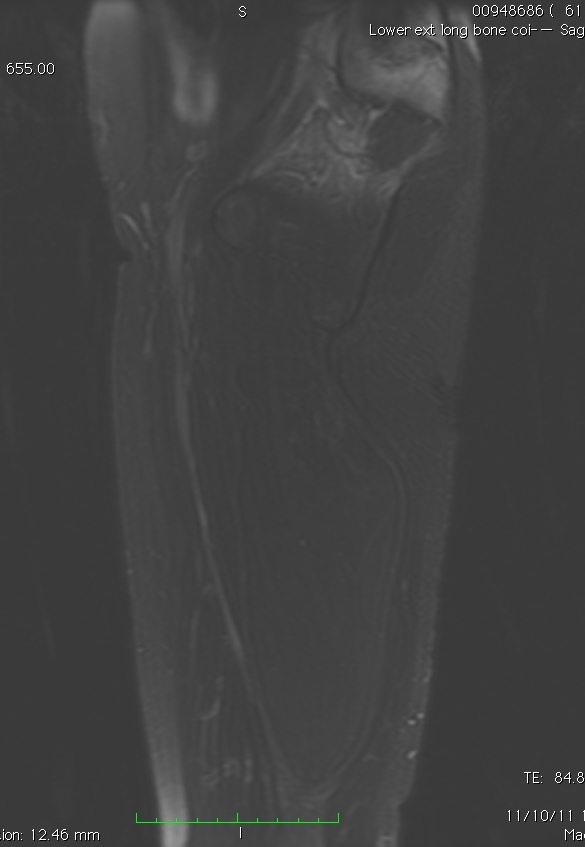

MRI

• Follows the signal characteristics of subcutaneous fat on all sequences

• T1: High Signal

• T2: Intermediate Signal; Low Signal with Fat Suppression

• Minimal or No enhancement with gadolinium

Fig. 1A, 1B, 1C, 2A, 2B, 2C: MRI of a lipoma: T1- weighted images shows an homogeneous mass in the posterior compartment of the thigh with high signal, saturates on fat saturated sequences with no or minimal enhancement. On T2-weighted images demonstrate an intermediate signal on FSE T2, saturates (becomes dark) on fat saturated sequences.